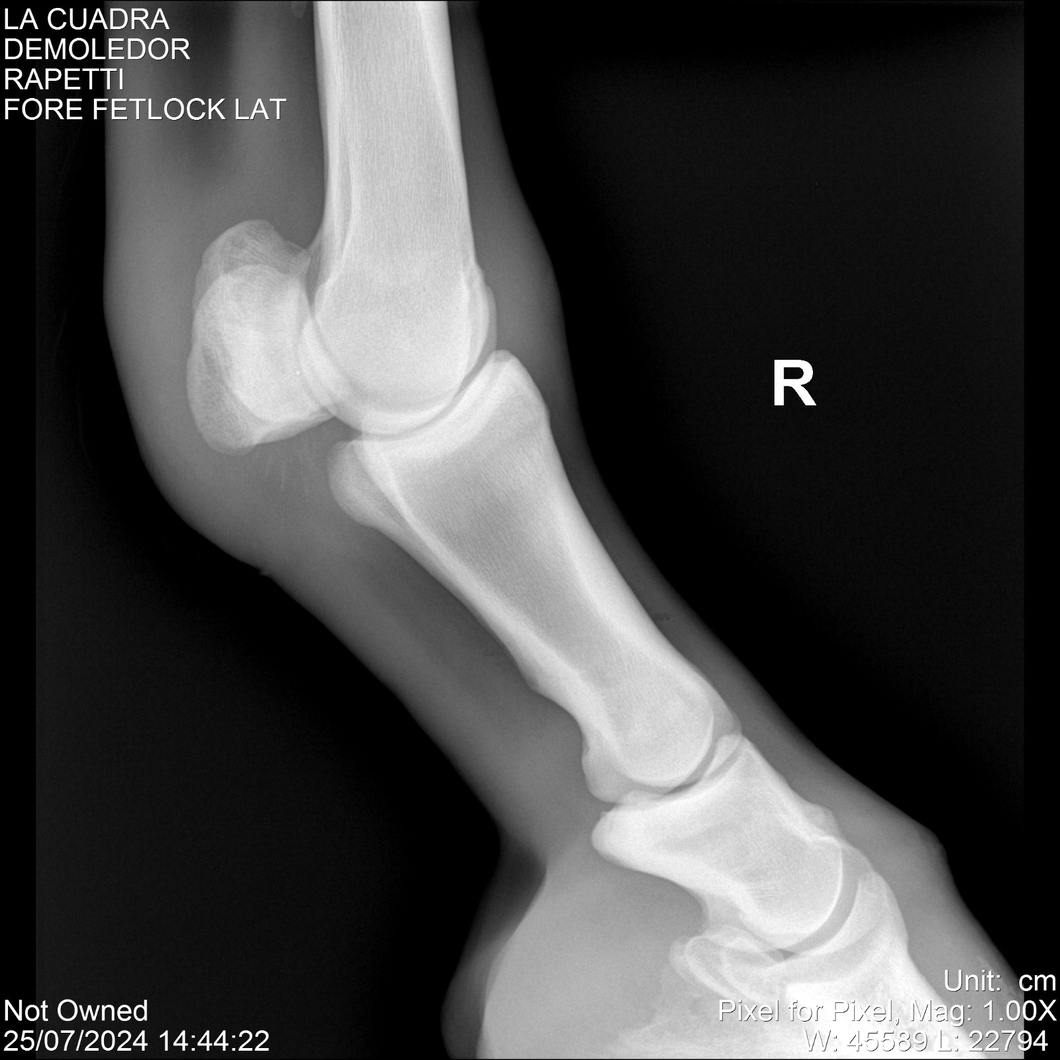

LOTE 14, DEMOLEDOR 🔥 🔥 🔥 Lote Anterior Volver al remate Lote Siguiente Ficha Contacto Montevideo - Ficha del Lote Identificador: #284454 Categoría: Yeguarizos Montevideo - 89 Visualizaciones ClicData Contacto Empresa: Abelenda N. R., Walter Hugo Nombre*: Teléfono* : E-mail* : Mensaje Enviar Registrese gratis Este contenido Exclusivo está disponible sólo para usuarios registrados Ingresar